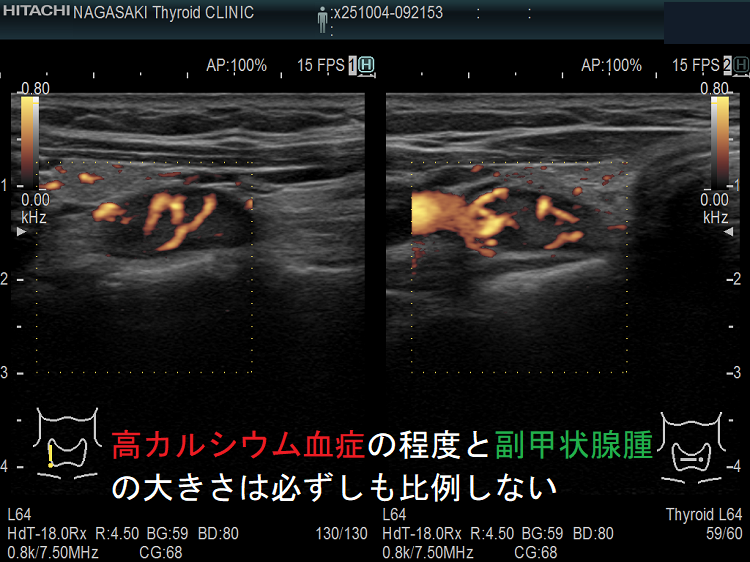

高カルシウム血症の程度と副甲状腺腫の大きさは必ずしも比例しない